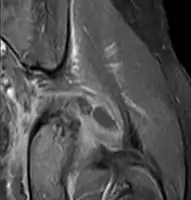

Axial T1 weighted fat suppressed post IV gadolinium contrast enhanced MRI image showing a mutliloculated bacterial abscess in the left gluteal muscle which grew Staphylococcus aureus (methicillin sensitive) thought to be due to tropical pyomyositis.

Coronal fat suppressed post contrast image showing a multiloculated bacterial abscess in the left gluteus minimus muscle due to tropical pyomyositis.